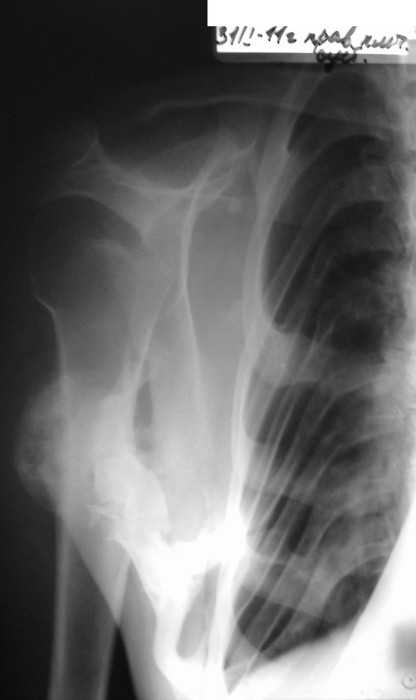

Вложение не в текстовом формате было извлечено…

Имя     : should11.JPG